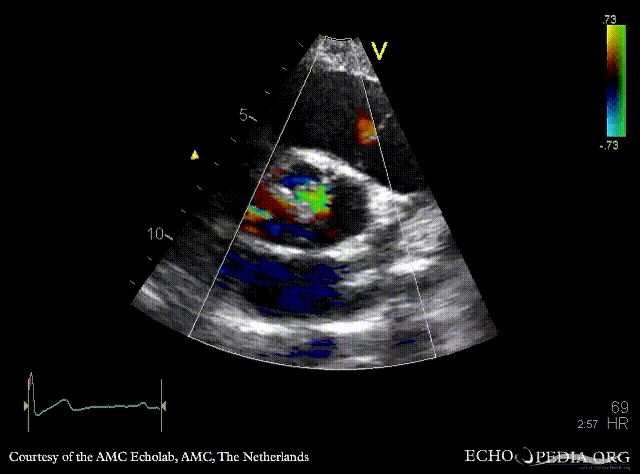

PLAX: dilated aortic root and left ventricle PLAX with Color Doppler: severe aortic regurgitation